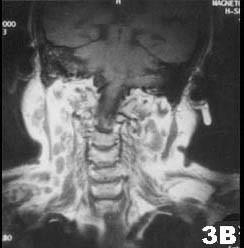

肺结核患者发现双侧腮腺区肿块3个月,缓慢增大,无明显症状。查体腮腺区可触及局限性肿块,边界清,质软,可活动,轻压痛。CT 检查结果图示。首先考虑的诊断为 ( )

A腮腺囊肿

B腮腺结核

C慢性腮腺炎

D腮腺腺样囊性癌

E腮腺多形性腺瘤